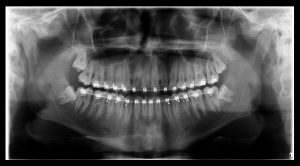

Radiografia Panorâmica

A radiografia panorâmica consiste em uma única incidência do complexo maxilomandibular. É uma das técnicas radiográficas mais solicitadas e difundidas em todas as especialidades da Odontologia.